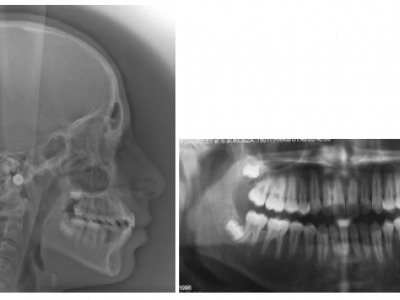

La téléradiographie montre la classe III squelettique et sur la radiographie panoramique on note un manque de place pour les dents définitives aux 2 arcades (Fig.3-9). 15 et 25 peu visibles à ce stade, ont un retard de minéralisation.

Dans le 1er cas, en observant les téléradiographies de profil, on note que bien que les incisives centrales supérieures soient en proalvéolie à la fin de la première phase de traitement (Fig. 8), comme l’occlusion normalisée est obtenue précocement (au moment de l’éruption des incisives), la croissance améliore spontanément leur inclinaison par le redressement des racines (Fig. 9).